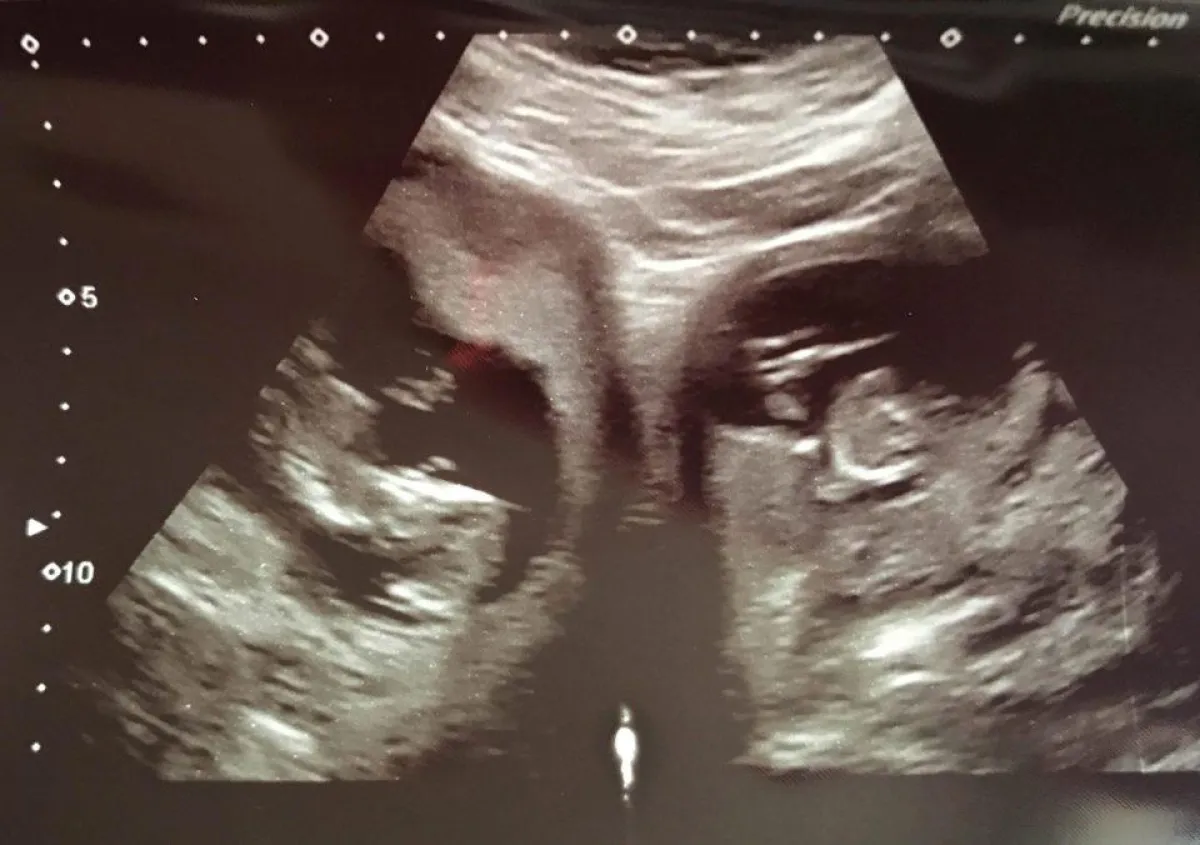

وكانت السيدة "جنفير آشوود" وزوجها "أندرو" الذي يعمل رجل إطفاء، قد اكتشفا خلال فترة حملها الأخير هذا من خلال التصوير بـ"الموجات الصوتية" أن لديها طفلين، كل واحد منهما ينمو في رحم على حدة، ويُشار بأن هذه الحالة النادرة، لا تتسبب في أي مشاكل إضافية للسيدة الحامل، لكن احتمالية الولادة المبكرة أو الإجهاض تكون مرتفعة قليلاً مقارنة بالنساء الطبيعيات.